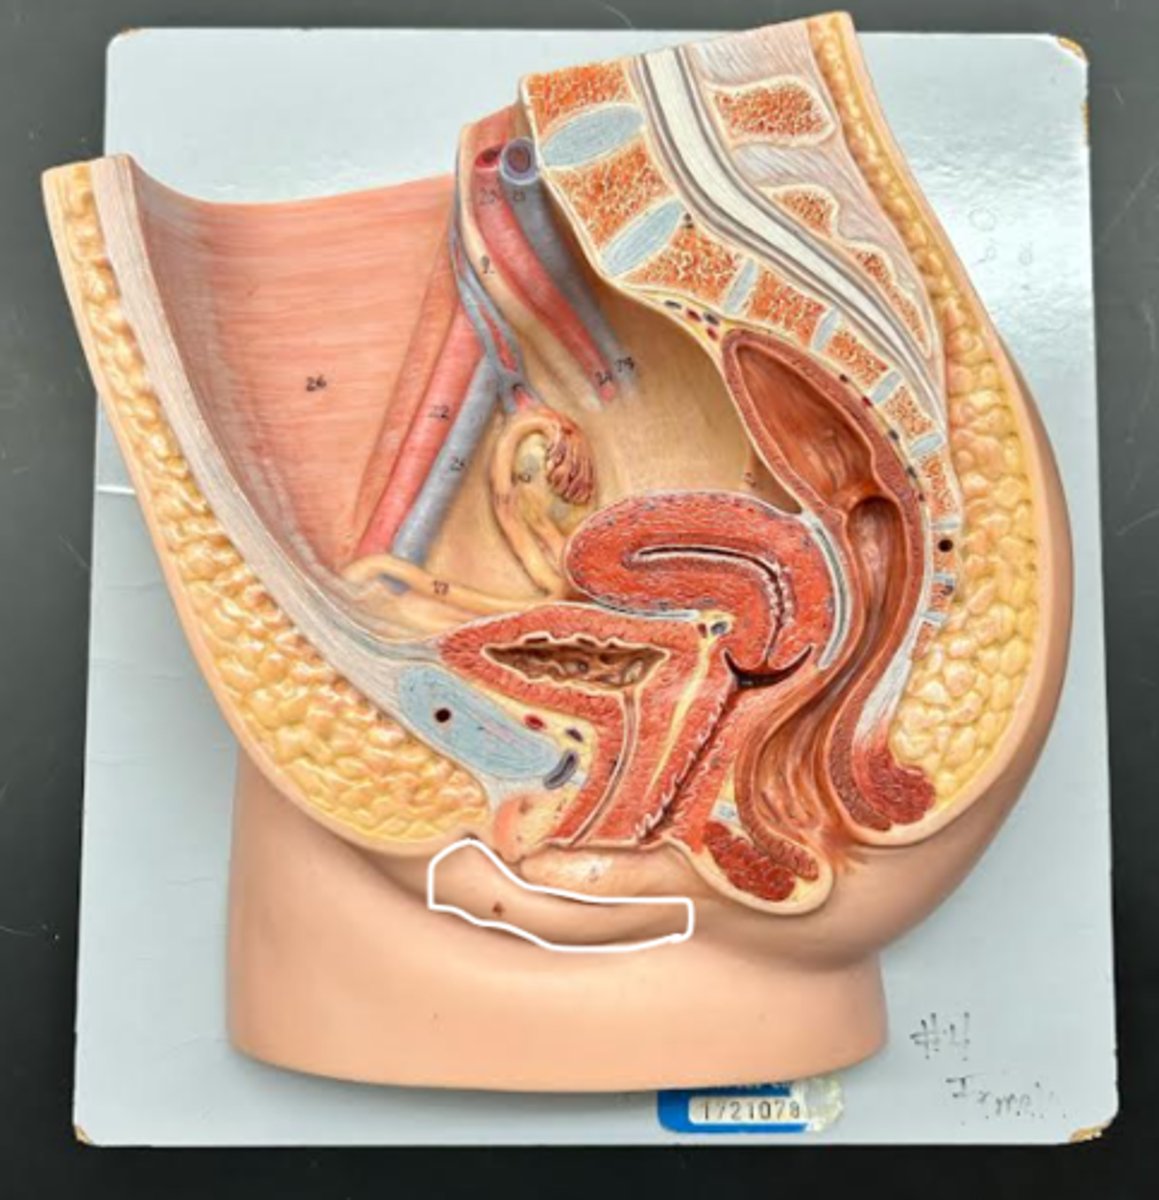

Labia majora

Labia minora

Prepuce

Vestibule

Clitoris

External urethral orifice